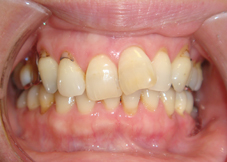

前歯のでこぼこと八重歯を気にされて来院されました。

左上の犬歯がかなり上から生えてきて八重歯になっています(左写真)。前歯の脇の歯は内側に入ってしまい前歯がでこぼこで、どちらの歯も磨きにくく汚れがたまりやすい状態です。

特に八重歯の状態は他の歯より上に位置するため磨き残されやすく、虫歯にしてしまいがちなので要注意です。

<治療開始前>

左上の犬歯が八重歯になっており、そのため上真ん中は大きく左へズレています。また本来、上の前歯は下の前歯に覆いかぶさらないといけないのですが、上下前歯は咬み合っていません。

<治療開始6ヶ月後>

歯が並ぶスペースが著しく不足しているためこれを解消すること、また上下の咬み合っていない前歯の状態を解消するために上下とも抜歯を行い治療を開始しました。治療開始から6ヶ月後、八重歯は改善しています。この後、上下の噛み合わせの改善を行いました。

<矯正治療後>治療期間22ヶ月

22ヶ月後、歯の移動を終了して装置を除去、保定に入りました。装置は表側の装置ですが目立ちにくいタイプのもの使用しています。材質はサファイアで透明度が高いため歯の色と馴染むのが特徴です。ワイヤーはホワイトワイヤーを使用してさらに目立ちにくくしています。